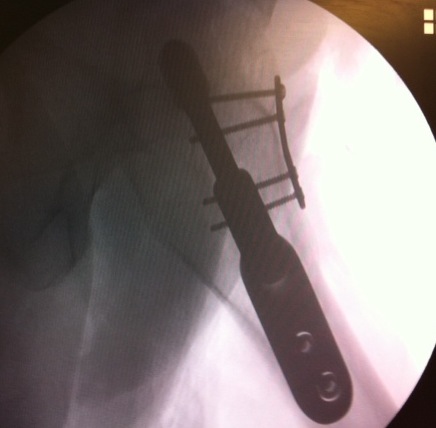

Fixation

DHS /Cannulated screws / FNS

Unstable fracture - augment with a medial buttress plate on inferior neck

Medial buttress plate